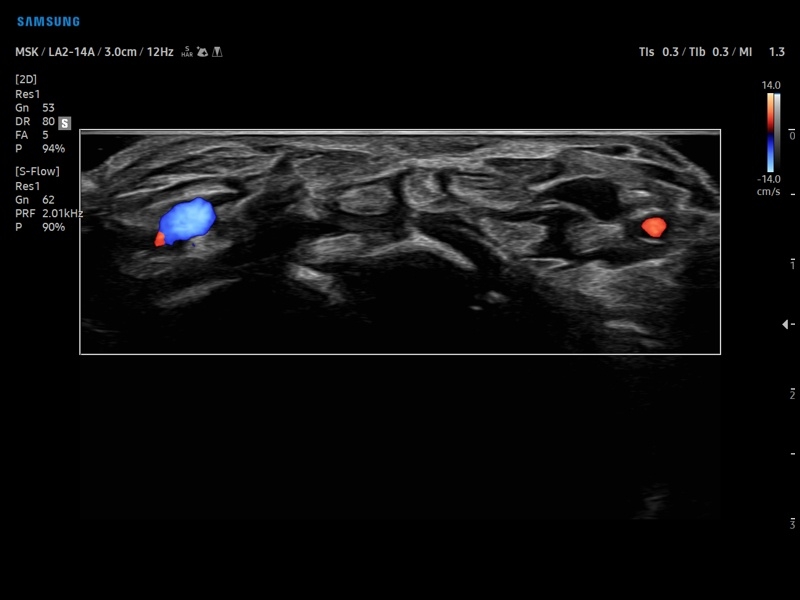

Недопплеровская визуализация кровотока:

Да

• CD - цветное допплеровское картирование с возможностью изменения допплеровского угла.

• PD - энергетический допплер с возможностью изменения допплеровского угла.

• DPDI - двунаправленный энергетический допплер.

• Расширенная сосудистая визуализация: Auto IMT+, 2D Arterial Analysis

• Модуль MV-Flow – программа (режим), позволяющая визуализировать кровоток в микроциркуляторном русле с высоким разрешением без использования контраста.

• Модуль LumiFlow – программа отображения кровотока с объемной графикой для лучшего понимания архитектоники сосудистого русла.

• Программа SEE Stream – режим недопплеровской визуализации кровотока в реальном масштабе времени.